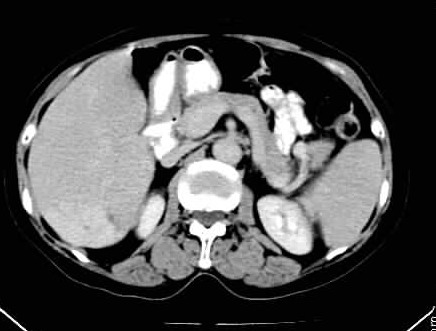

标题: CT24035:肝内占位

肝右叶后段低密度块影,增强后造影剂逐渐向病灶充填,支持肝血管瘤。

右叶后段血管瘤,层面少,看不见左叶,脾大。

肝右叶后段血管瘤、肝左叶缺如、脾大